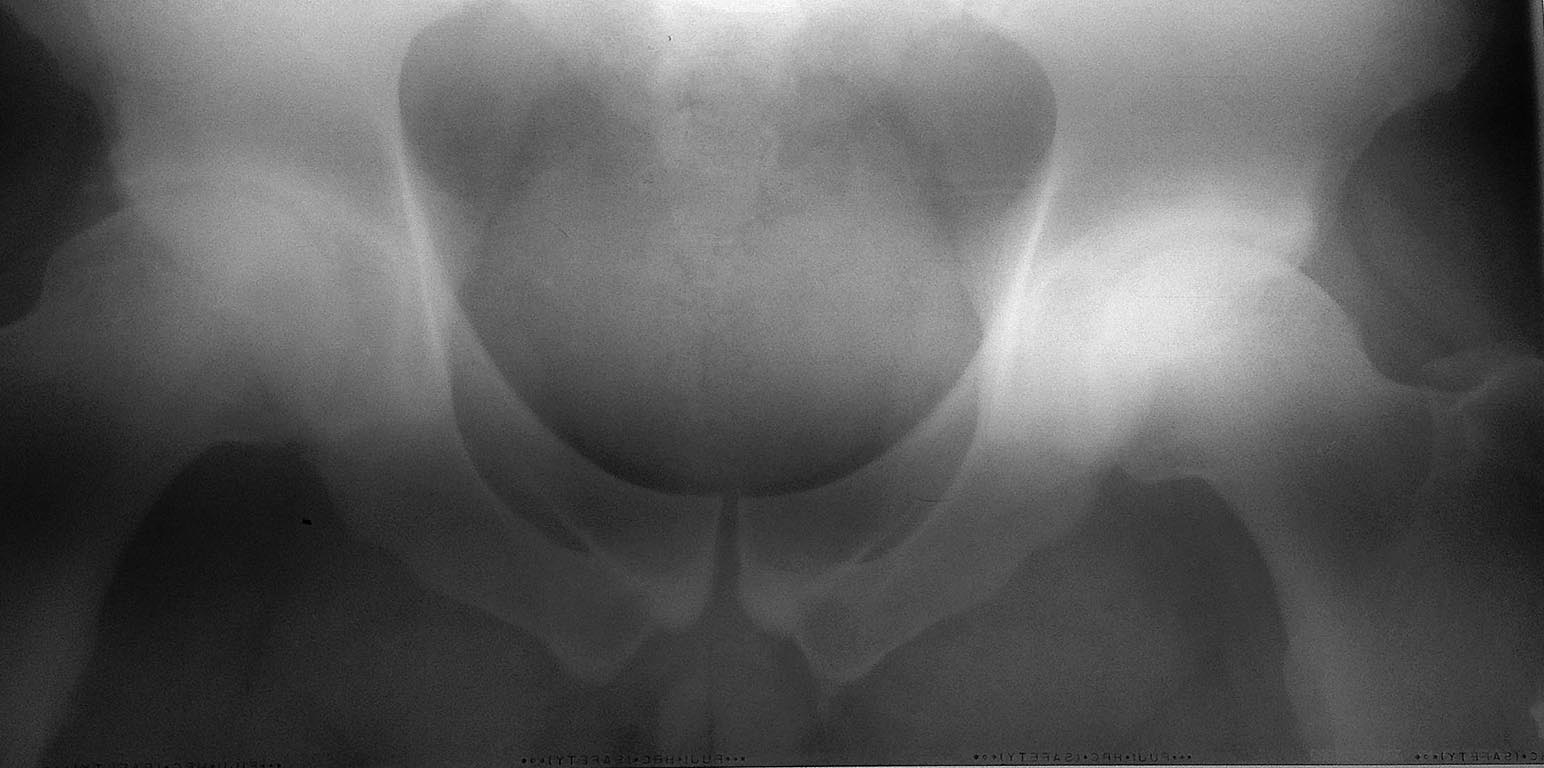

молодой активный человек , спортсмен наш коллега. резкая боль при стереотипных движениях,наружная ротация и разгибании. МРТ будет близко. Рентген - что выжал. МРТ будет. Вопросы:1 шейвироваать с рыеиксацией губы? 2 открытый хиругиечский вывих, 3 подождать и эндоротез?

заранее извиняюсь за качество, в ближайшее время переделаю.

Еще раз извиняюсь за качество снимков, это так, в плане скрининга. В ближайшее время постараюсь выложить человеческие снимки, включая False Profile, КТ с 3D, MРТ (c гадолинием не обещаю). Буду выкладывать, по мере получения информации.

Максим! Импиджмент налицо. Делайте что угодно, что сможете, только не ждать. В конце концов отправьте в Рниито им Вредена. Открытый вывих не лучший вариант. Но! При подобных снимках и клинике предлагал операцию неоднократно. Не хотят. ( ну я же не хромаю). Доводы на перспективу не работают :(

Судя по снимкам, остеоартроз на фоне импинджемента только 2 стадии, МРТ, конечно, более детально покажет состояние хряща. А консервативно уменьшить болевой синдром и продлить срок службы сустава пациет не желает? Можно при соблюдении ортопедического разгрузочного режима сначала провести СМ-форез с дексаметазоном и новокаином №10, затем УВТ с внутритканевой электростимуляцией по 7 процедур, параллельно при необходимости параартиркулярные блокады (наропин+дипроспан) под УЗ контролем №1-3. Затем ввести протез синовиальной жидкости и после пусть позанимается с врачом ЛФК индивидуально, можно по методике NEURAC с использованием подвесных систем REDCORD. Если эффекта не будет или на МРТ серьезное локальное повреждение хряща, то решать проблему оперативным путем. Ну это так, как возможный вариант.